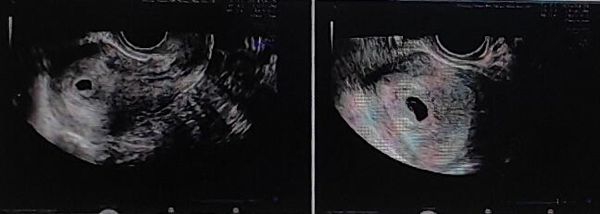

经过超声及AMH检查评估,卵巢功能尚可。但考虑已经33岁了,徐士儒主任建议其生育要抓紧,不可再拖延。

考虑既往有盆腔手术史,加上超声检查之后综合评估宫腔环境并不适合马上进行鲜胚移植,王燕医生嘱咐小李先不要着急,适当调养好身体,改善子宫内膜,为胚胎移植做相关准备。